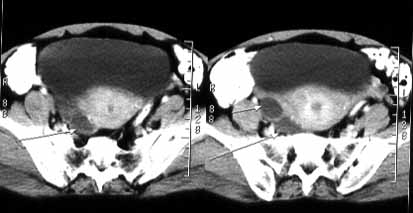

Complex cyst on ovary is cyst that contains both solid and liquid components. This type of ovarian cyst has more serious outcome if compared to normal ovarian cyst, therefore it is definitely cannot be treated lightly. Unlike the normal cyst which will usually resolve itself in a matter of months, complex ovarian cyst has the potential to grow and bleed within its capsule and sometimes, twist the ovary.

Complex cyst on ovary is different from the polycystic ovarian disease, PCOD. Though it can be seen on ultrasound report, it is not clear and usually not distinct. Complex cyst is different from mixed cystic and solid cysts however in which the anatomy is clearer but of mixed consistency.

More often than not, complex ovarian cyst is follicle cyst that with bleeding in it and inflammatory processes. There are 3 types of ovarian cyst complex, namely Dermoid Cysts, Endometrioma, and Cystadenomas.